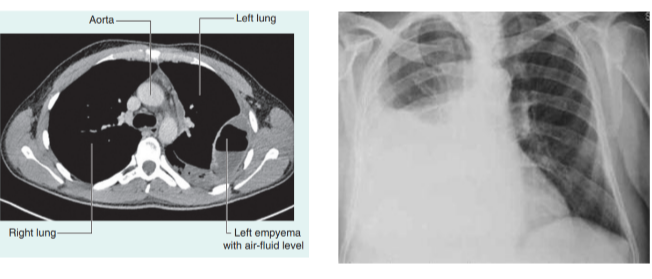

Clinical drop — pleural effusion

Occurs when excess fluid accumulates within the pleural space

As the fluid accumulates within the pleural space the underlying lung is compromised and may collapse as the volume of fluid increases

The fluid will usually be aspirated to determine the cause, which could be —

Infections, malignancy, cardiac failure, hepatic disease, pulmonary embolism

A large pleural effusion needs to be drained to allow the collapsed part of the lung to reexpand and improve breathing